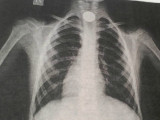

تارازدىق دارىگەرلەر وڭەشىندە تيىن تۇرىپ قالعان بالانى امان الىپ قالدى

تارازدىق دارىگەرلەر وڭەشىندە تيىن تۇرىپ قالعان 9 جاستاعى بالانى قۇتقاردى, دەپ حابارلايدى Egemen.kz وبلىستىق دەنساۋلىق ساقتاۋ باسقارماسىنىڭ ءباسپاسوز قىزمەتىنە سىلتەمە جاساپ.